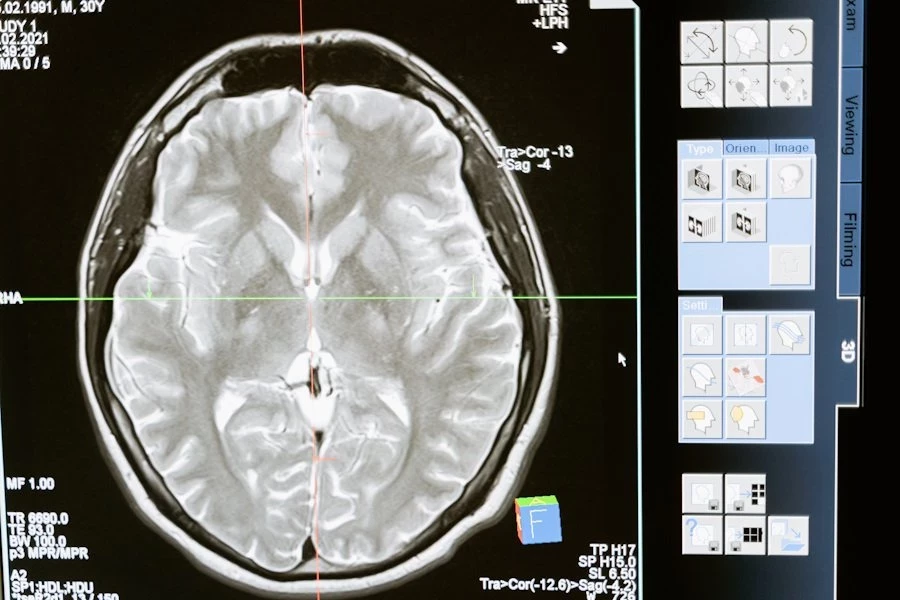

Ученые УрФУ синтезировали новое вещество с противоопухолевыми свойствами, которое может стать основой препарата для лечения глиобластомы — одной из самых агрессивных форм рака центральной нервной системы. Ожидается, что лекарство на его основе будет менее токсичным для пациентов по сравнению с существующими аналогами. Подробности исследования опубликованы на портале BioMetals, сообщает РИА Новости.

Глиобластома является наиболее распространенной злокачественной первичной опухолью головного мозга. Она чаще всего поражает лобные, височные, теменные и затылочные доли мозга и встречается преимущественно у людей старше 64 лет, причем мужчины страдают от этого заболевания чаще, чем женщины, отмечают ученые УрФУ.